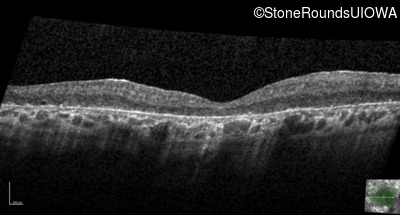

Optical Coherence Tomography - Left - Light Perception

Exemplar / OCT Stack

OCT Stack